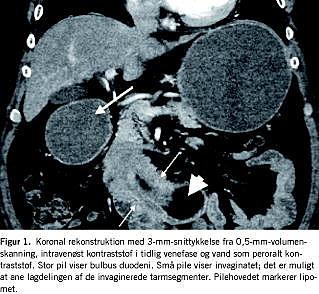

En tidligere rask, 60-årig mand med body mass index på 36 blev henvist efter fem måneders varende tiltagende symptomer på ventrikelretention i form af pyrosis, kvalme og opkastninger samt mavesmerter og et vægttab på 13 kg. Patienten havde haft en episode med blødning per rectum og anæmi (hæmoglobin: 5,2 mmol/l). Ved gastroskopi fandt man ventriklen svært forstørret, og der påvistes et ulcus i en svært deformeret bulbus duodeni uden blødning. Ulcus blev skleroseret og der blev iværksat Helicobacter pylori-eradikationsbehandling. Ved en kontrolgastroskopi fire uger senere fandt man udtalt ventrikelretention og et stenoseret parti i duodenums andet stykke, som ikke var passabelt for skopet. Kontrastpassage af ventrikel og duodenum viste, at duodenum var klemt af en rundagtig udfyldning. Ved computertomografi (CT) af abdomen sås et okkluderende, hypodenst vævsområde i 2.-3. stykke af duodenum, som var fri af pancreas (Figur 1). Det blev primært tolket som invagination som følge af et stort tarmvægslipom.

I udredningen af den gastroduodenale invagination indgår typisk endoskopi, røntgenkontrastundersøgelse, ultralydskanning og CT [2, 5]. Det er beskrevet, at en tidlig CT af abdomen med fund af target sign (målskivekonfiguration), som er karakteristisk for invagination, er den bedste diagnostiske metode [3]. I dette tilfælde fandt man ved CT, at invagination var den mest sandsynlige diagnose. Andre mulige tolkninger var pancreas annulare eller torkveret tarm. I de fleste rapporterede tilfælde, og som i dette, blev diagnosen først stillet endeligt ved den eksplorative laparotomi, men CT- af abdomen har vist sig at være særdeles værdifuld i diagnostikken [2, 3, 5].